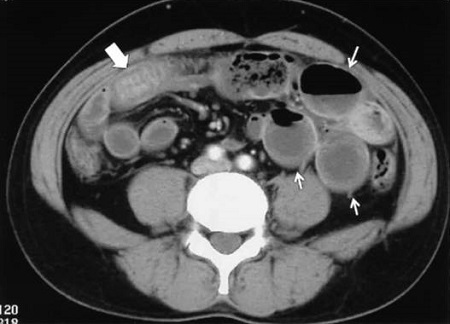

小腸アニサキス症

腹部CT検査で腸管浮腫、腸閉塞を認めれば見当つきます。顔面、体感のアニサキスアレルギーを疑う発疹も参考になります。確定診断は、小腸カプセル内視鏡ですが、もし見つけてもカメラは届かないのでアニサキスを捕れません。

軽症例は7日程度でアニサキス虫体の死亡により改善するので対症療法で良いですが、重症例は開腹手術になります。

(造影CT画像 岡山医学会雑誌(2009)121, 25-27)